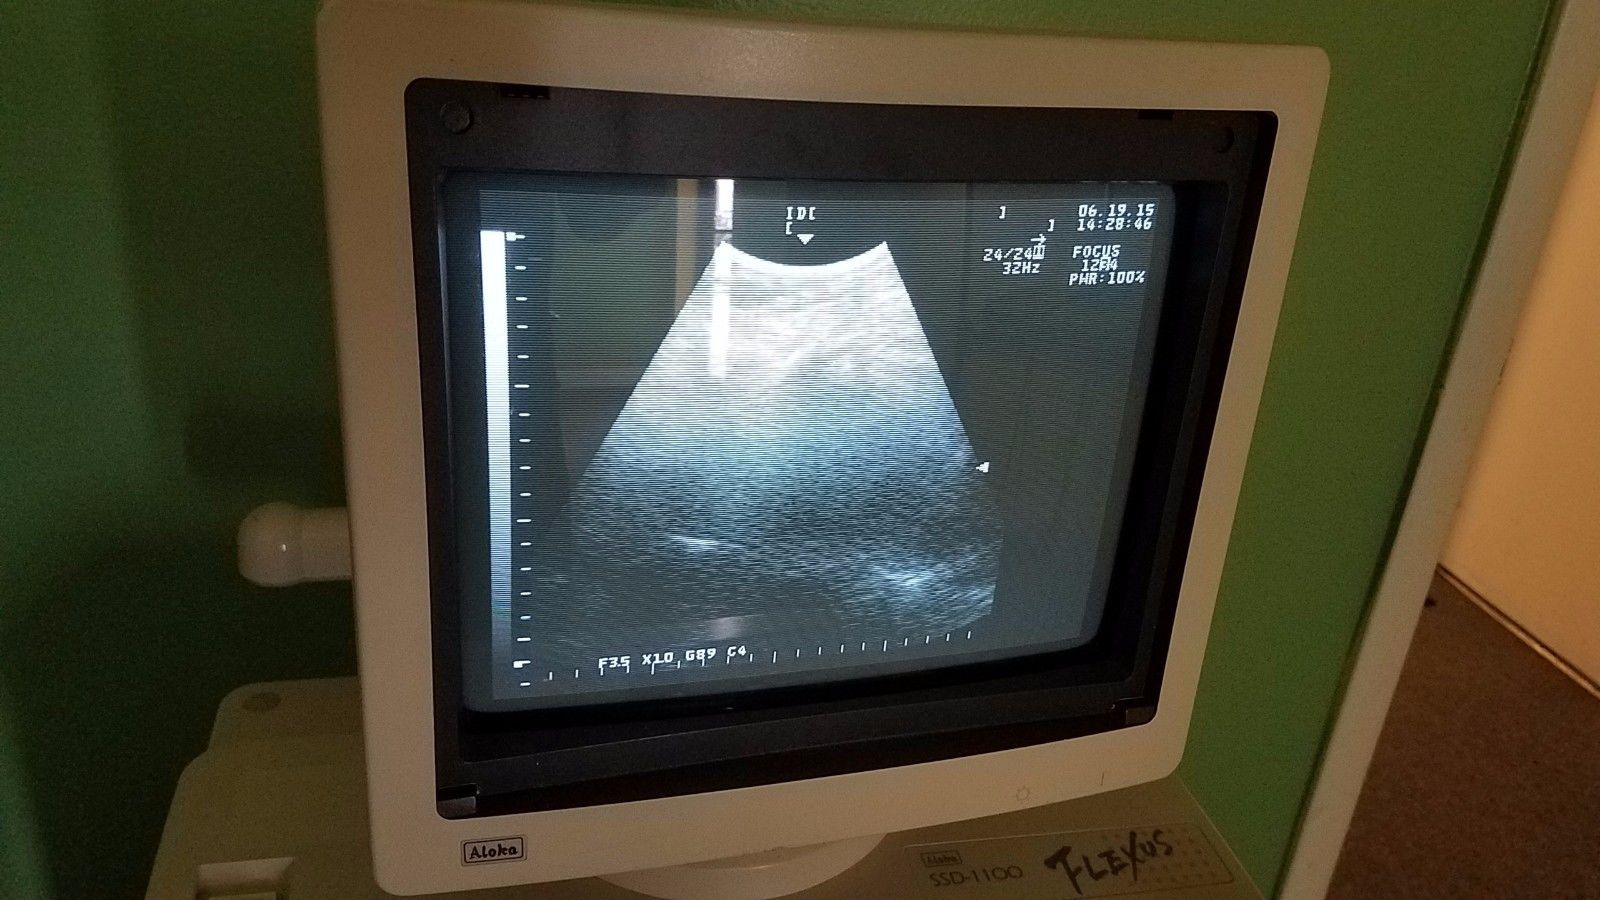

DIAGNOSTIC ULTRASOUND MACHINES FOR SALE

DIAGNOSTIC ULTRASOUND MACHINES FOR SALE

DIAGNOSTIC ULTRASOUND MACHINES FOR SALE